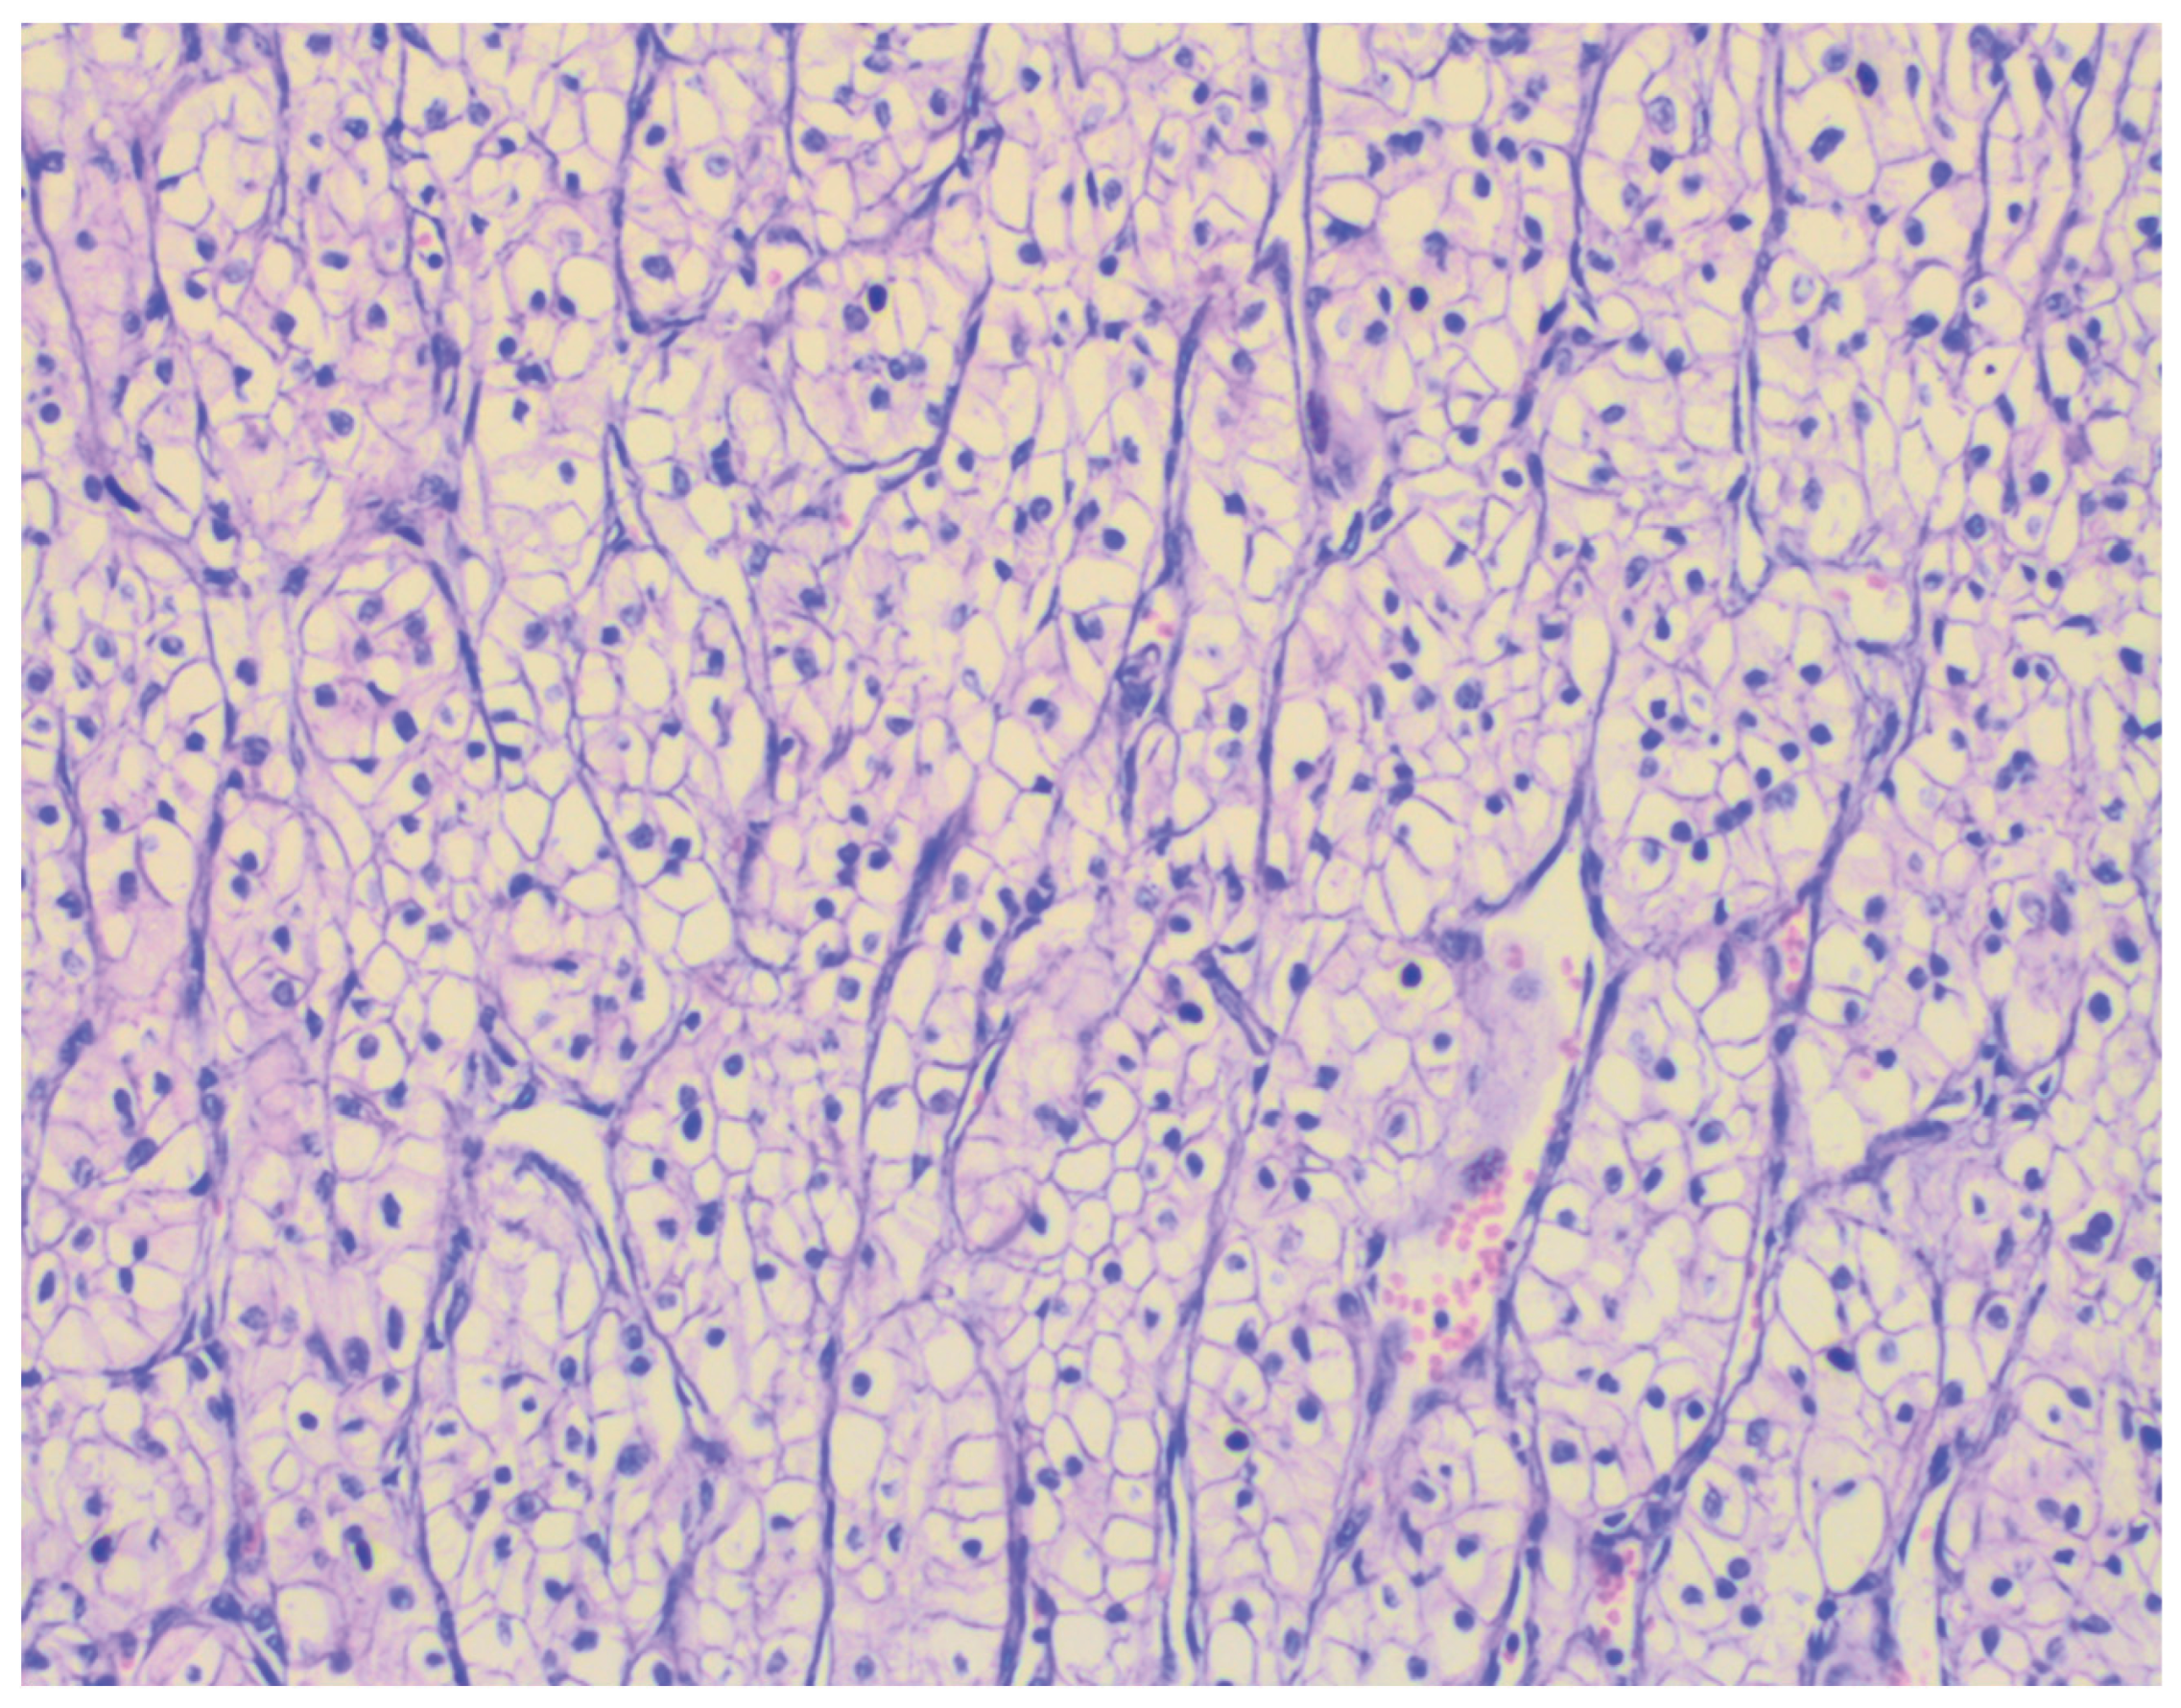

Histopathological examination revealed nests and alveolar arrangements of atypical clear cells with optically empty cytoplasm, well-defined cell borders, and hyperchromatic nuclei, organized around thin-walled, branching blood vessels. Foci of necrosis and hemorrhage were also observed. These morphological features were consistent with metastatic ccRCC, confirming secondary involvement of the urinary bladder from a primary renal tumor (

Figure 3).

Immunohistochemical profiling further corroborated the diagnosis of metastatic ccRCC with bladder involvement. Tumor cells exhibited positive staining for PAX8, CD10, and CAIX, and were negative for CK7 and GATA3. This immunophenotype is characteristic of ccRCC and allows clear distinction from primary urothelial carcinoma [